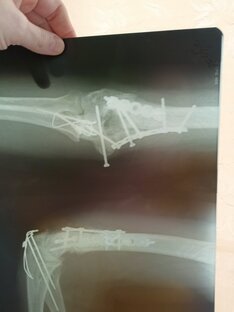

Началось все с перелома. Если не вдаваться в медицинскую терминологию, то сломался у меня сустав. Честно говоря - это жесть. Любой перелом требует неподвижности, только в этом случае нарастает нужная соединительная ткань, которая потом превращается в костную. Обычно перелому нужно около месяца, чтоб нормально схватится. Сустав зафиксировать сложно, невольно организм делает микро-движения, которые мешают срастанию. А сращивать-то надо много. Сустав фиксируют надолго - полная иммобилизация на два месяца, фиксирующая повязка - ещё на месяц...

Хочешь восстановиться - спроси меня как